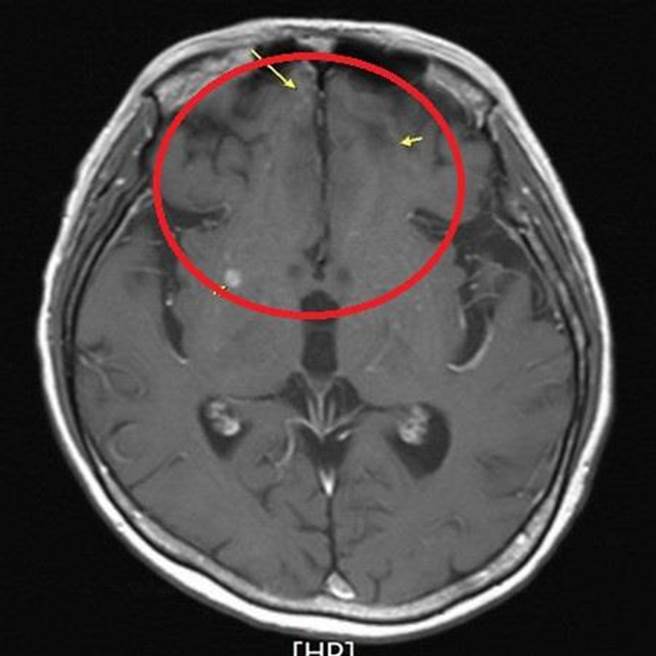

经抗体复合药物治疗后,脑部转移的癌细胞明显缩小。(台北慈济医院提供)

张耀仁副院长决定予以新型的抗体复合药物,加上放射性治疗,半年后,脑部转移肿瘤明显缩小,刘小姐已能自由行走,癌指数也回到正常范围内。